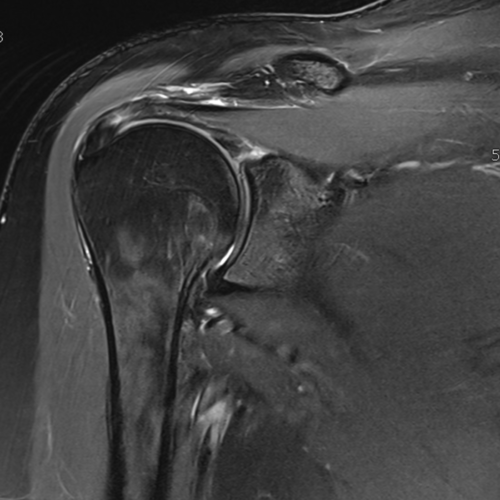

Cet examen est réalisé pour analyser les différentes structures anatomiques du rachis cervical : tête humérale, glène, labrum, tendon supra-épineux, infra-épineux, sub-scapulaire, articulation acromio-claviculaire, bourse sous acromiale.

Quels sont les résultats possibles d’une IRM de l’épaule ?

Cette examen permets de diagnostiquer:

- les tendinites

- les ruptures de coiffe

- les capsulites

- les omarthroses

- les luxations et arthroses acromio-claviculaires

- les bursites sous acromiales

- les fissures tendineuses

- les lésions du labrum : Bankart, Perthes, ALPSA,

- Les syndromes de Parsonage Turner

- Les bursites BSAD